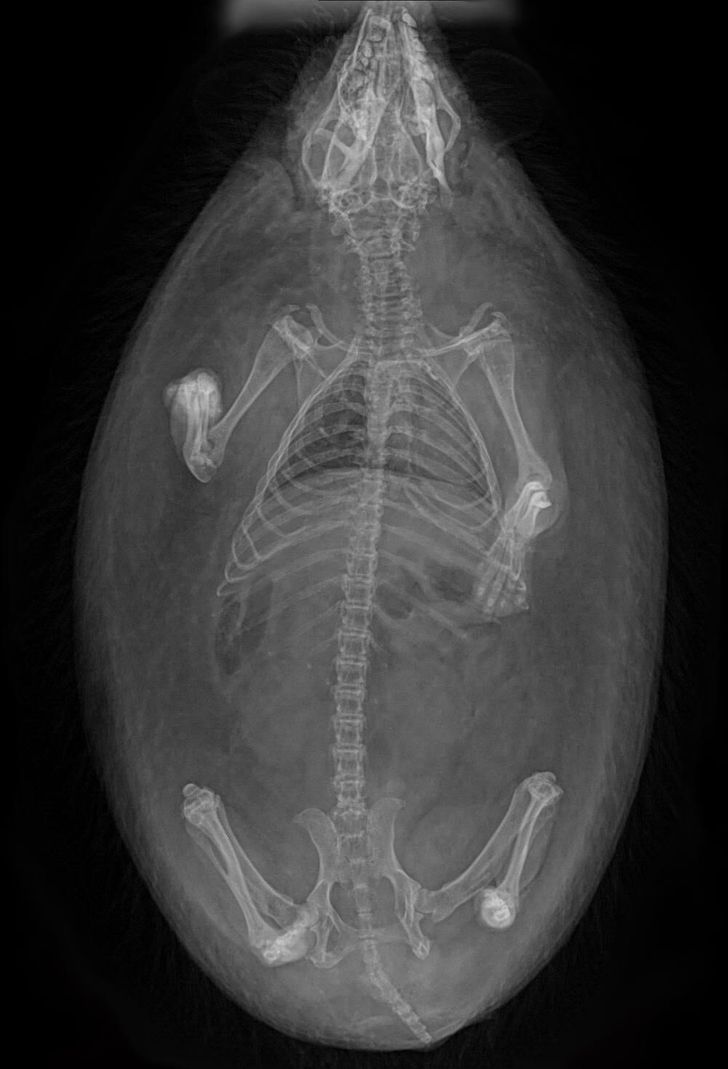

7. We never knew hedgehogs could be so fascinating!

Illustration de l'article : 14 X-ray images that reveal a hidden story

© DragonsExMachina / Reddit